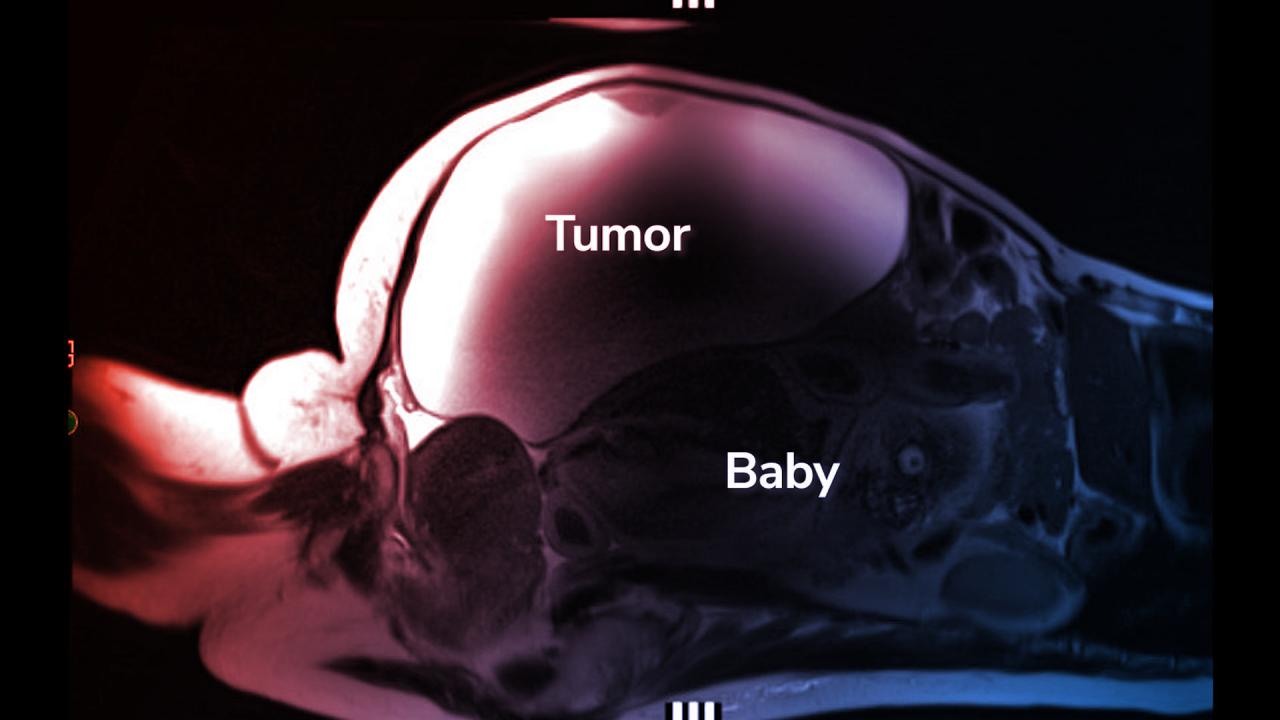

A nő Los Angelesben, a Cedars-Sinai Medical Centerben esett át az életmentő beavatkozáson, amit mintegy harminc egészségügyi dolgozó koordinált. Idővel a vizsgálatok – többek között MRI- és ultrahangvizsgálat – egyértelművé tették, hogy Lopeznél egy ritka hasi méhen kívüli terhesség áll fenn, amikor a magzat a méh helyett a hasüregben fejlődik. A baba a mája közelében helyezkedett el, hátával a méh tetején pihenve. Az ilyen típusú terhességek rendkívül veszélyesek, és szinte példátlanok, hiszen a magzatnak rendkívül csekély a túlélési esélye.

A beavatkozás alatt mind a cisztát, mind a gyermeket sikerült biztonságosan eltávolítani. Lopez súlyos vérzés miatt kis híján életét vesztette, de az orvoscsoportnak, amely 11 egység (körülbelül 5,2 liter) vérrel pótolta a veszteségét, sikerült stabilizálnia az állapotát. A baba, aki a Ryu nevet kapta, és 3,6 kilogrammal született, azonnal a koraszülött intenzív osztályra került, de az orvosok szerint meglepően jó állapotban volt. Dr. Fadi Bsat, a neonatológus hangsúlyozta, hogy a kisfiú minden várakozást felülmúlt, és gyakorlatilag meghazudtolta az orvosi tankönyveket.